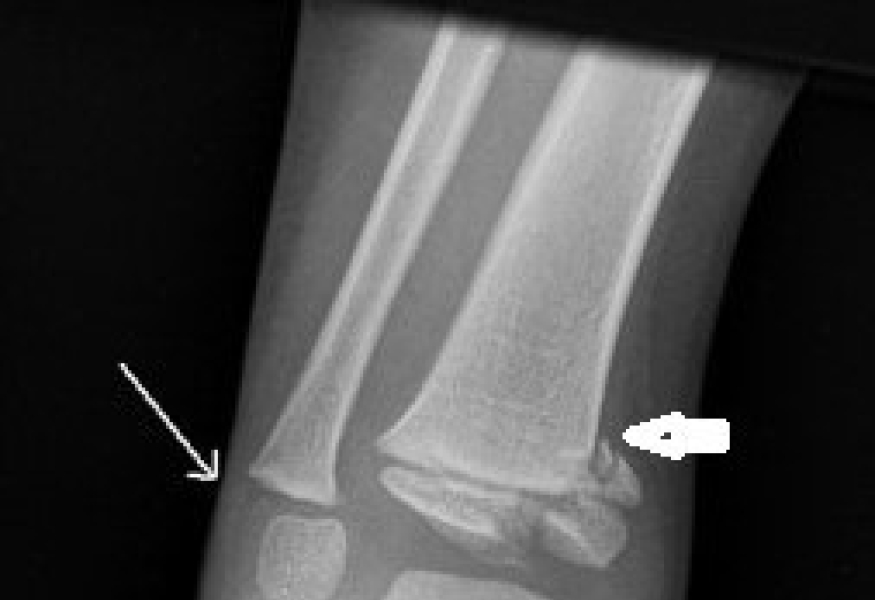

An X-ray is the most common way to look at an ankle fracture. The physician also looks at the growth plates to check for injury.

The arrows on this X-ray show the growth plate fractures.